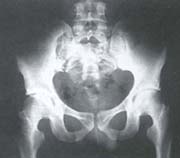

Paciente de 65 años, sexo femenino quien consulta por dolor sacroiliaco derecho, diagnosticándose mediante biopsia sacroileitis tuberculosa. Luego de ocho semanas de tratamiento farmacológico, se efectúo abordaje posterior por línea media de columna lumbosacra y fijación con barras iliosacras.

Fig. 7E Vista radiográfica anteroposterior de la técnica.